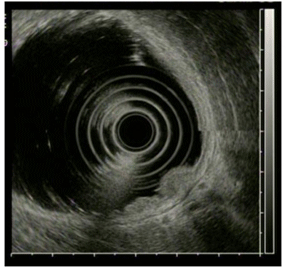

3. 내시경적 초음파 내시경 (EUS : endoscopic ultrasonography)

내시경 끝에 초음파 진단 장치를 붙여 병변을 검사하는 것으로 종양이 위벽에 얼마나 깊이 침범했는지 주변 림프선에 전이가 없는지 위암의 진행 정도 및 전이 여부를 자세하게 검사하는 방법이다. 모든 환자에게 시행하는 검사는 아니며 주로 위암의 치료를 위하여 내시경 점막하 절제술의 적용 가능성을 평가하기 위해 사용한다.